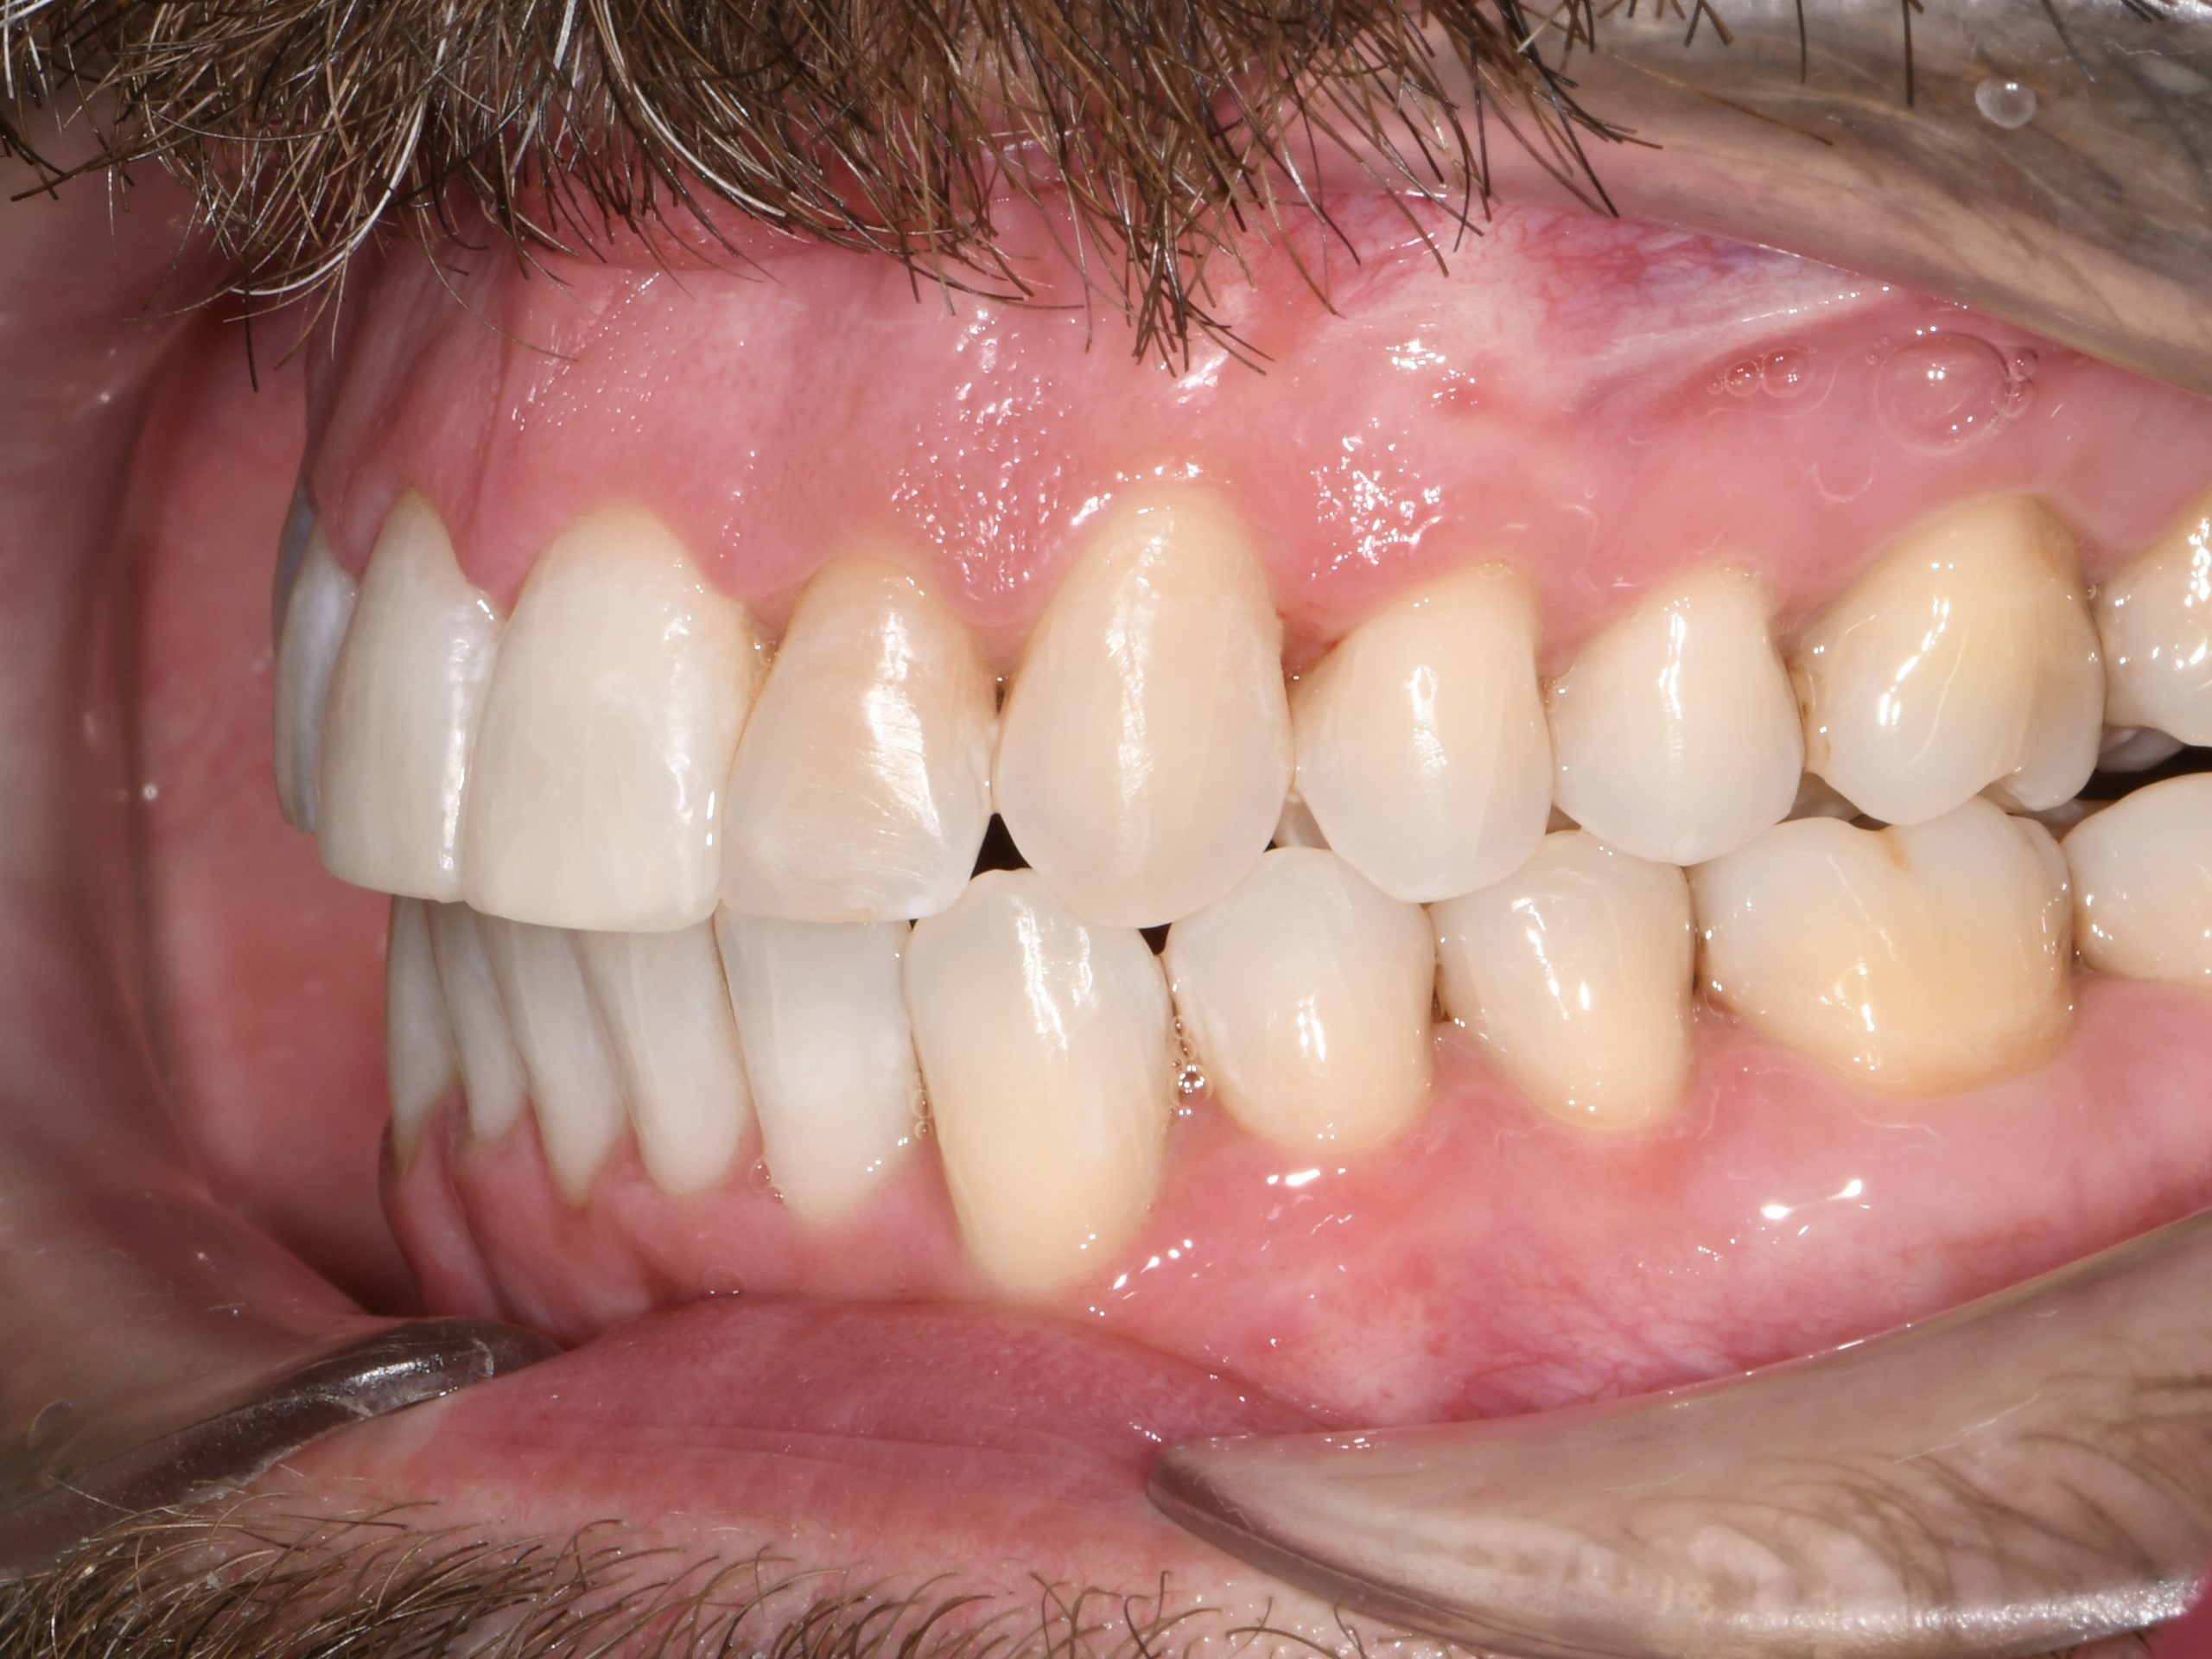

Az elmúlt évekből rengeteg szakmai referenciát tudnánk bemutatni, amelyek különböző fogszabályozási problémákat oldottak meg. Válogatva a több száz esetből, ezen az oldalon olyan képeket, információkat igyekeztünk bemutatni, amelyeknek a segítségével a jövőbeni pácienseinknek azt tudjuk üzenni: A Te fogsorod is lehet gyönyörű!

(Képeket a Pácienseink külön írásos beleegyezésével mutatjuk be!)